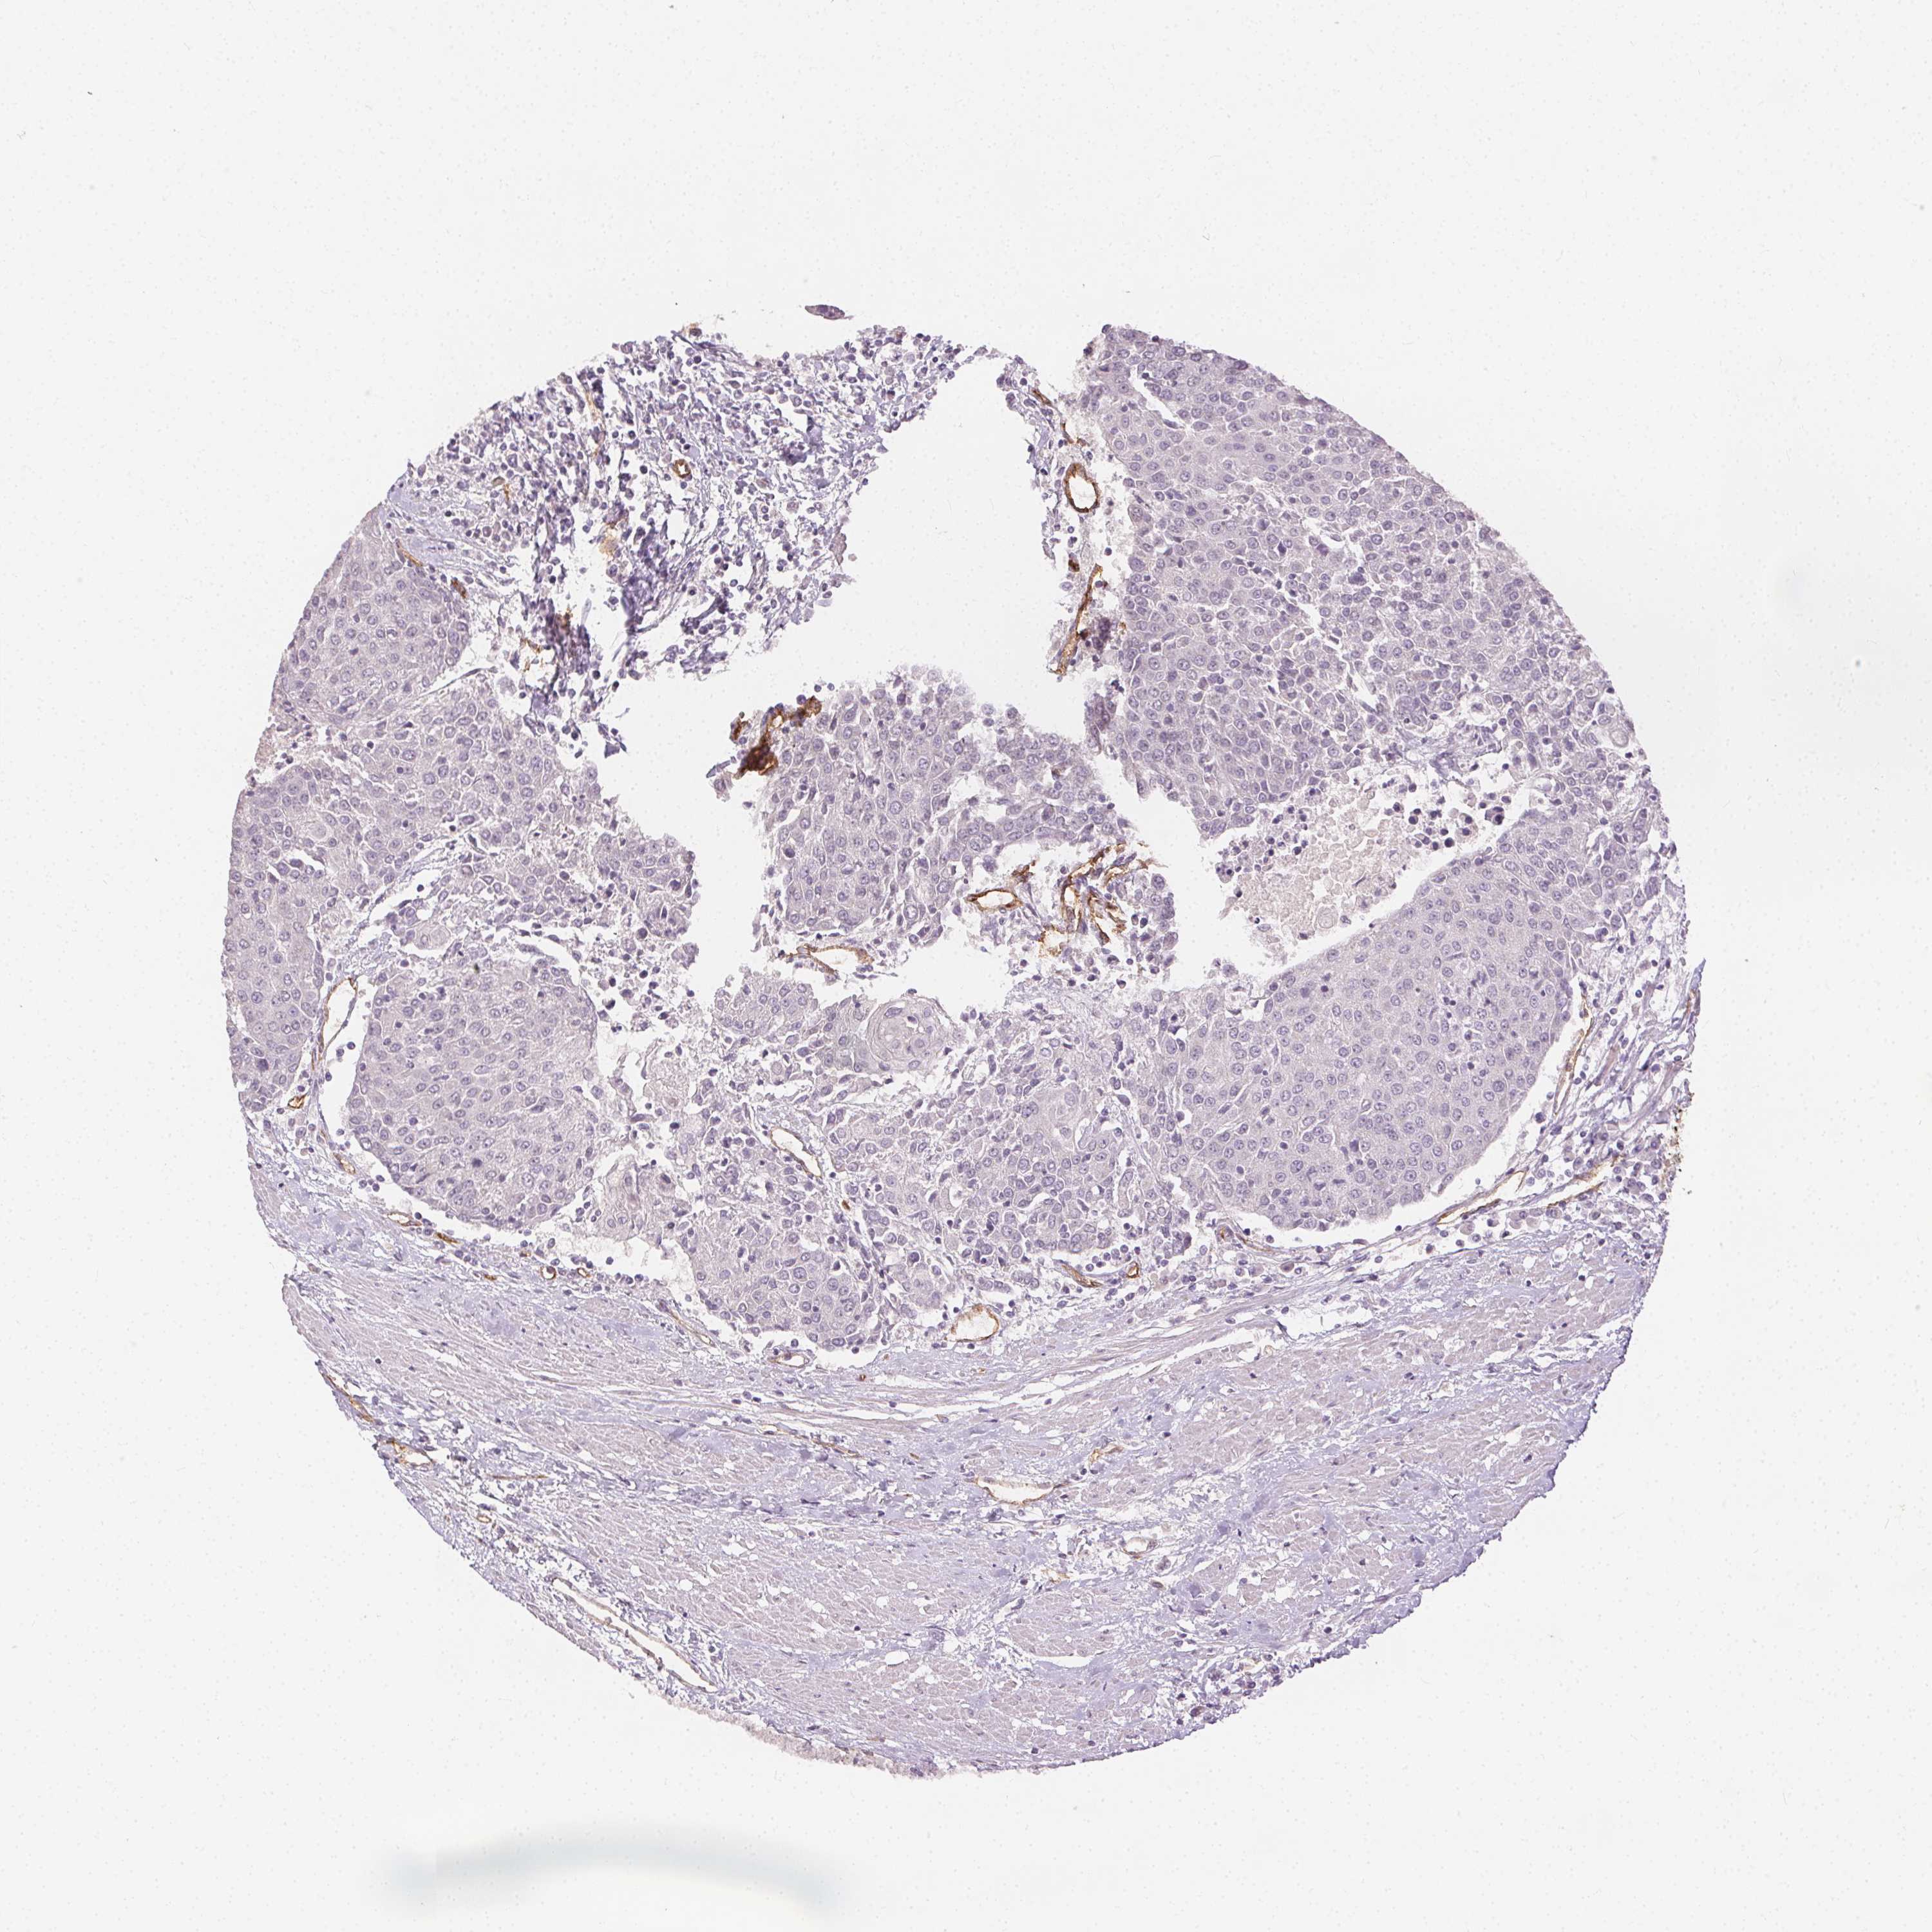

UROTHELIAL CANCER - Protein expressioni

A mouse-over function shows sample information and annotation data. Click on an image to view it in a full screen mode. Samples can be filtered based on level of antibody staining by selecting one or several of the following categories: high, medium, low and not detected. The assay and annotation is described here.

Antibody stainingi

Antibody staining in the annotated cell types in the current human tissue is reported as not detected, low, medium, or high, based on conventional immunohistochemistry profiling in selected tissues. This score is based on the combination of the staining intensity and fraction of stained cells.

Each image is clickable and will lead to virtual microscopy that enables deeper exploration of all samples and also displays staining intensity scores, fraction scores and subcellular localization as well as patient and tissue information for each sample.

HPA002110

HPA045507

CAB016169

CAB062558

CAB068219

CAB068220

Staining

High

Medium

Low

Not detected

Intensity

Strong

Moderate

Weak

Negative

Quantity

>75%

75%-25%

<25%

None

Location

Nuclear

Cytoplasmic/membranous

Cytoplasmic/membranous,nuclear

Urothelial carcinoma, High grade

Urothelial carcinoma, NOS

Urothelial carcinoma, Low grade